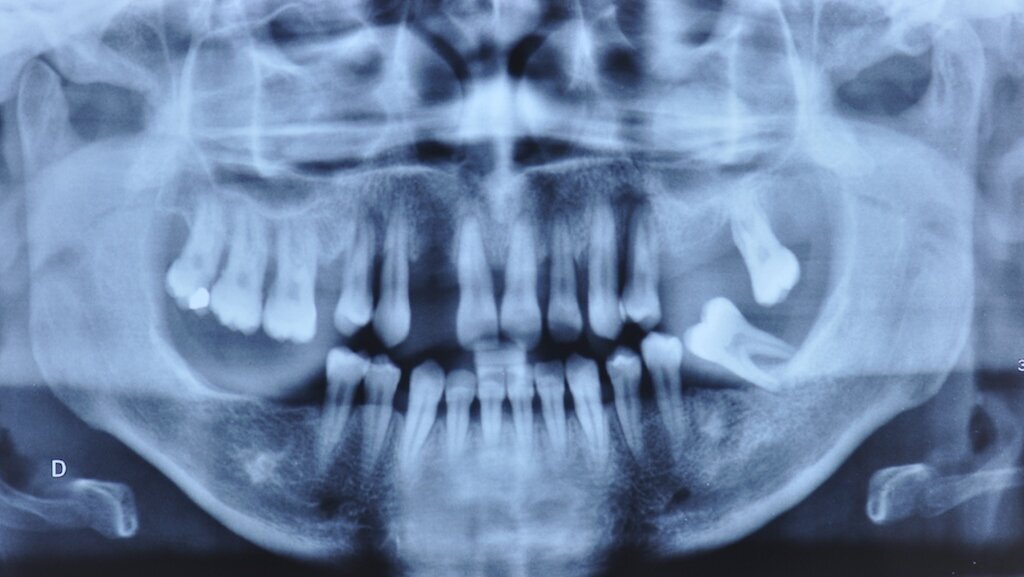

Le cas clinique présenté est celui d’une patiente de 40 ans, adressée en consultation de parodontologie par son praticien traitant (Fig. 1). La patiente a été motivée à consulter en raison d’une mobilité accrue de ses dents, et une vestibulo-version récente et rapide de ses incisives maxillaires, ce qui lui procure un inconfort esthétique (Fig. 2). Elle rapporte également des épisodes douloureux de plus en plus fréquents du côté gauche. La patiente ne présente pas de problème de santé particulier. Elle est cependant fumeuse modérée (5 cigarettes par jour) et exprime une certaine anxiété vis-à-vis des soins dentaires. Les dents 27 et 37 sont extraites en urgence puis la patiente est prise en charge pour une réhabilitation globale. Enfin, un bilan radiographique rétro-alvéolaire (Fig. 3) permet de préciser le diagnostic dento-parodontal.

· Parodontal : les symptômes de mobilité, le niveau radiologique de l’os alvéolaire et l’âge de la patiente orientent le diagnostic vers une parodontite agressive à progression rapide, aggravée par le tabac. Le pronostic est sans espoir pour les dents 14, 24, 27, 37. Il est réservé pour les autres dents maxillaires : 18, 17, 16, 13, 11, 21, 22, 23. Il est acceptable pour les dents mandibulaires de 35 à 45.